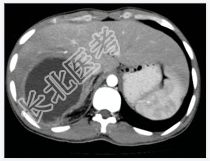

- [材料题] 患者男性,25岁,因发热.肝区疼痛2周入院。2周前患者无明显诱因出现高热.肝区疼痛,血常规检查白细胞及中性粒细胞明显升高。体查.肝肋缘下1cm可触及,且有明显触痛。行上腹部CT增强扫描+三维重建。

- 简答题1、患者的诊断及依据是什么?

- 简答题2、鉴别诊断有哪些?